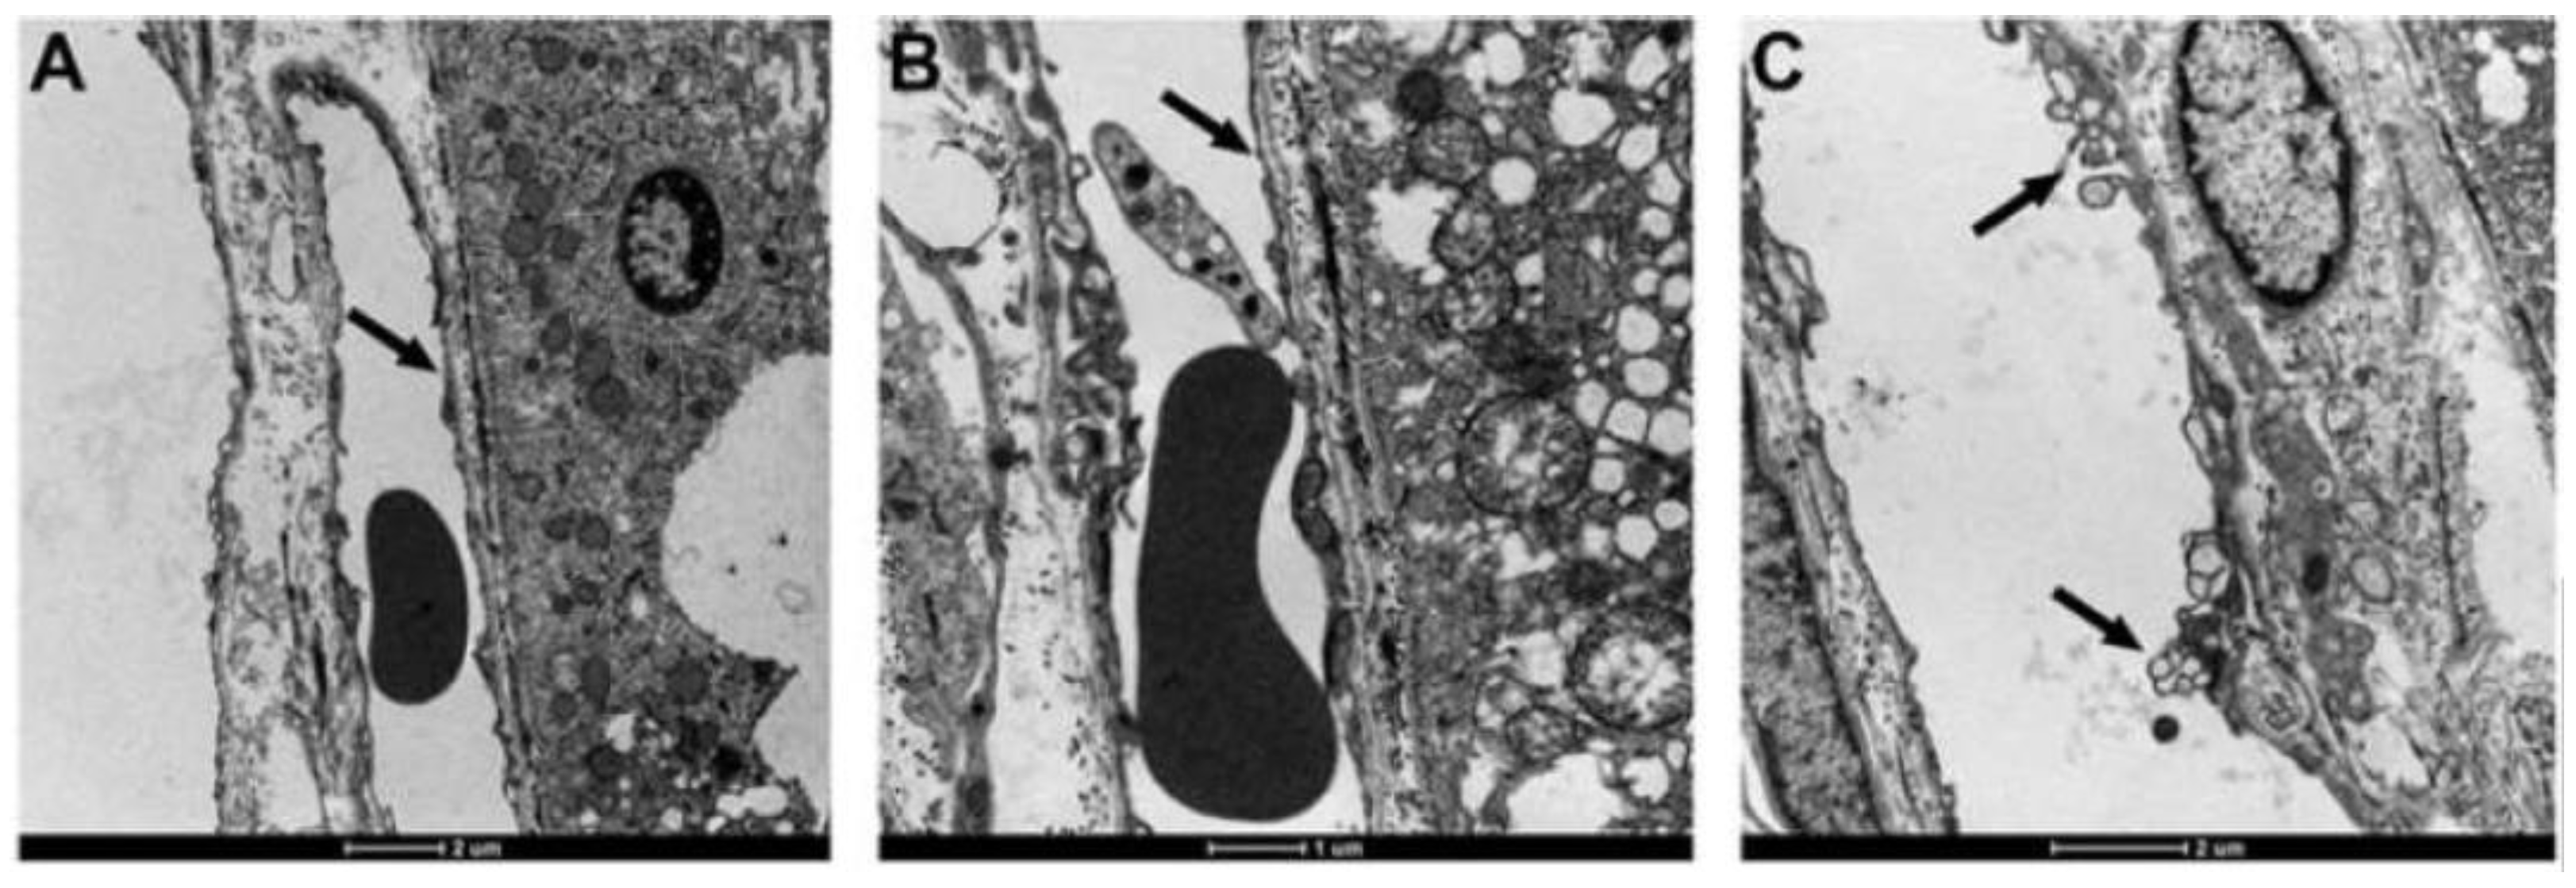

In the first study of ETX-induced retinal injury in rats [23], six-week-old, Sprague Dawley animals were given an intraperitoneal injection of a 1:300 dilution of a batch of ETX, which was equivalent to 69,000 mouse minimum lethal doses of this toxin. At 3 h post-injection of toxin, rats were killed by perfusion fixation with 4% paraformaldehyde, with one eye then fixed in Davidson’s fixative for light microscopy and the other with 2.5% glutaraldehyde for electron microscopy. For the immunohistochemical detection of plasma albumin extravasation, a goat anti-rat albumin antibody was used. Control rats were given a similar volume of physiological saline and their eyes were similarly processed. When rats were given this acute dose of ETX [23], severe ultrastructural retinal microvascular injury was found. The most severe endothelial damage was characterized by marked attenuation and increased electron density (Figure 1). Prior to the development of endothelial coagulation necrosis, there was frequent blebbing of the luminal surface and occasional platelet adhesion (Figure 1), but not thrombosis. These retinal microvascular lesions resembled those found in the brain microvasculature of sheep [2,3] and mice [24] exposed to ETX (Figure 2). To further examine this BRB breakdown, immunohistochemical studies used endogenous albumin extravasation as a surrogate marker of increased vascular permeability [23]. In ETX-treated rats, there was diffuse albumin extravasation in all retinal layers, which was particularly prominent around small blood vessels, and albumin also flooded the cytoplasm of damaged endothelial cells (Figure 3). This widespread retinal albumin leakage confirmed the presence of generalized vasogenic oedema and resembled the albumin extravasation found in ETX-exposed sheep (Figure 4) [2,3] and rat brains [23]. Microvascular albumin leakage is particularly deleterious to the retina as regulation of albumin transport is critical for maintaining appropriate protein gradients in the retina and subsequent fluid movement [12,13].

Figure 1.

Electron micrograph of ETX-induced coagulation necrosis of the retinal microvasculature (arrows) in a rat, this damage evidenced by marked attenuation and electron-density of the endothelium (A,B). Less severe injury is represented by focal blebbing and multivacuolation (C). Uranyl acetate and lead citrate. Bar = 2 µm.